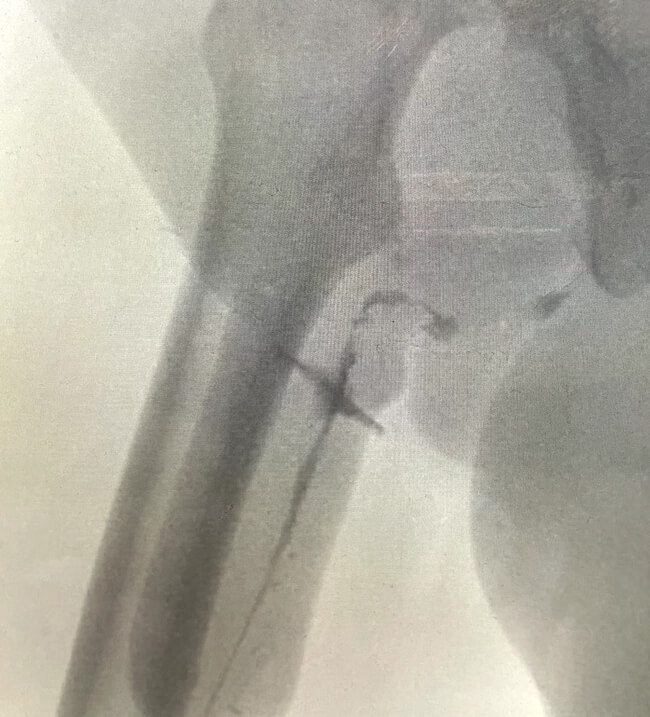

Figure 4: Urethrogram showing a urethrocutaneous fistula.

The most common urethral complication after a phalloplasty is a urethrocutaneous fistula (Figure 2 and 3) with an incidence of 15-70% [6]. Assessment of concomitant urethral strictures is mandatory in these patients (Figure 4). The most common sites for strictures are at the anastomotic sites in phalloplasty or metoidioplasty. The management is more challenging than for individuals assigned male at birth due to the more tenuous blood supply and lack of a corpus spongiosum. Fistulae tend to occur along previous suture lines or at anastomotic sites. A referral to the specialist unit for further investigation and management should be done. If the leaks from the fistulae are bothersome for the patient, then an SPC can be inserted. Other indications for SPC insertion include recurrent infection or excoriation of skin.